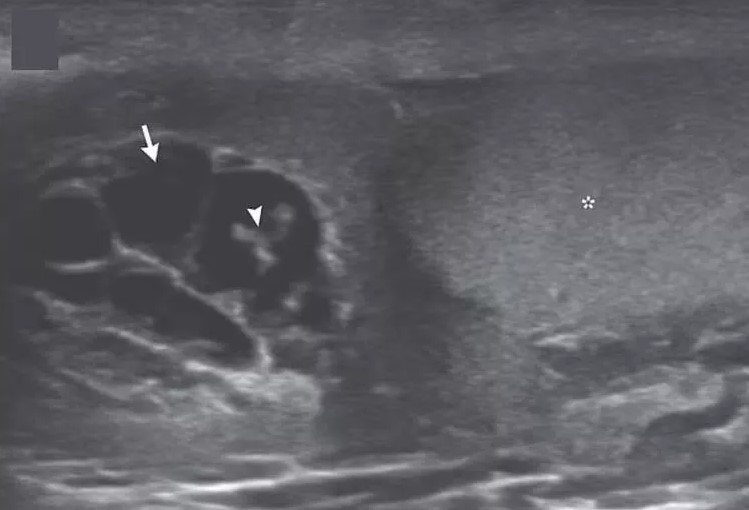

Hindistan'da meydana gelen olay sosyal medyayı salladı. Şişme şikayeti ile hastaneye başvuran adı açıklanmayan adamın skrotumunu mercek altına doktorlar gördükleri manzara sonrasında adeta şoke oldu.

İngiliz Daily Mail gazetesinde yer alan habere göre, doktorlar hastanın skrotumunda hareket eden doğrusal yapılar keşfetti.

Nadir görülen enfeksiyon, New England Journal of Medicine tarafından yayınlanan bir vaka raporu ile ortaya çıktı. Hastayı muayene eden Max Süper Özel Hastanede kıdemli tıbbi danışman olan Dr. Amit Sahu, ultrasonda 'doğrusal yapıların hareket ettiğini' söyledi.

Sahu gözlemledikleri hareket eden doğrusal yapılar için 'dans edecen düzinelerce solucan' ifadesini kullandı. Sahu, 'Lenf sistemine göç ederek kanalların genişlemesine ve işlev bozukluğuna neden oldular' dedi.